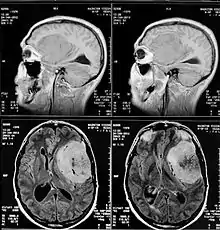

МРТ

В настоящее время МРТ с контрастным усилением является ведущим методом диагностики менингиом практически любой локализации. МРТ позволяет визуализировать васкуляризацию опухоли, степень поражения артерий и венозных синусов, а также взаимоотношения между опухолью и окружающими структурами. На нативных T1-взвешенных МРТ большинство менингиом не отличаются по интенсивности от коры головного мозга. Фиброматозные менингиомы могут быть по интенсивности и ниже коры. На T2-взвешенных МРТ менингиомы обычно повышенной интенсивности, отек также хорошо виден на T2-взвешенных МРТ. Интенсивное контрастное усиление выявляется у 85% менингиом. У менингиом часто встречается так называемый «дуральный хвост», участок прилежащей ТМО, интенсивно накапливающий КВ. Эта ТМО может быть как опухолево, так и реактивно измененной. «Дуральный хвост» встречается у 65% менингиом и только у 15% других опухолей. Поэтому он хотя и не специфичен для менингиомы, но позволяет более точно высказаться в её пользу. Среди недостатков этого метода необходимо отметить высокую частоту ложноотрицательных результатов в отношении диагностики наличия кальцинатов и очагов кровоизлияний.

КТ

КТ с контрастированием сопровождается умеренным-выраженным гомогенным усилением в большинстве случаев. При помощи КТ диагностируются около 90% менингиом. Главная роль КТ – демонстрация изменения костей и кальцинатов в опухоли.